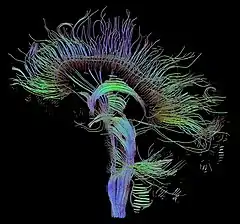

The principal application is in the imaging of white matter where the location, orientation, and anisotropy of the tracts can be measured. The architecture of the axons in parallel bundles, and their myelin sheaths, facilitate the diffusion of the water molecules preferentially along their main direction. Such preferentially oriented diffusion is called anisotropic diffusion.

The imaging of this property is an extension of diffusion MRI. If a series of diffusion gradients (i.e. magnetic field variations in the MRI magnet) are applied that can determine at least 3 directional vectors (use of 6 different gradients is the minimum and additional gradients improve the accuracy for "off-diagonal" information), it is possible to calculate, for each voxel, a tensor (i.e. a symmetric positive definite 3×3 matrix) that describes the 3-dimensional shape of diffusion. The fiber direction is indicated by the tensor's main eigenvector. This vector can be color-coded, yielding a cartography of the tracts' position and direction (red for left-right, blue for superior-inferior, and green for anterior-posterior).[45] The brightness is weighted by the fractional anisotropy which is a scalar measure of the degree of anisotropy in a given voxel. Mean diffusivity (MD) or trace is a scalar measure of the total diffusion within a voxel. These measures are commonly used clinically to localize white matter lesions that do not show up on other forms of clinical MRI.[46]

- Diffusion tensor imaging data can be used to perform tractography within white matter. Fiber tracking algorithms can be used to track a fiber along its whole length (e.g. the corticospinal tract, through which the motor information transit from the motor cortex to the spinal cord and the peripheral nerves). Tractography is a useful tool for measuring deficits in white matter, such as in aging. Its estimation of fiber orientation and strength is increasingly accurate, and it has widespread potential implications in the fields of cognitive neuroscience and neurobiology.